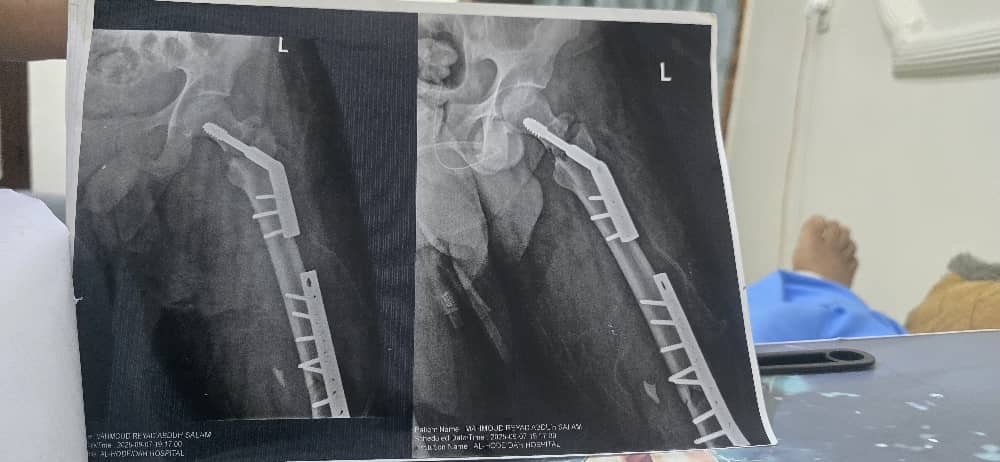

حادث مروري بثلاث كسور في الرجلين

السلام عليكم لقد تعرضت لكسر في عظمة الفخد واجريت عمليه زراعة اسياخ بلاتين وبراغي قبل عشرين يوم وبعد العمليه لاحظت...